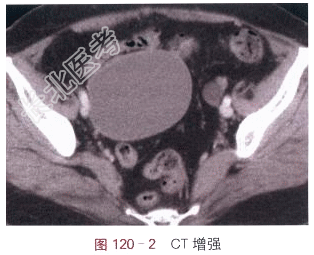

- [材料题] 女,78岁,自觉腹部肿块3月余。体格检查:右下腹肿块,边界清,质地软。影像学资料如图120-1~图120-2所示。

读片分析:右侧附件区见直径8cm类圆形囊性灶,密度均匀,囊内未见分隔;囊壁薄,未见壁结节,未见异常强化。左侧附件区也见直径1.5cm类圆形囊性灶,密度均匀,未见强化。